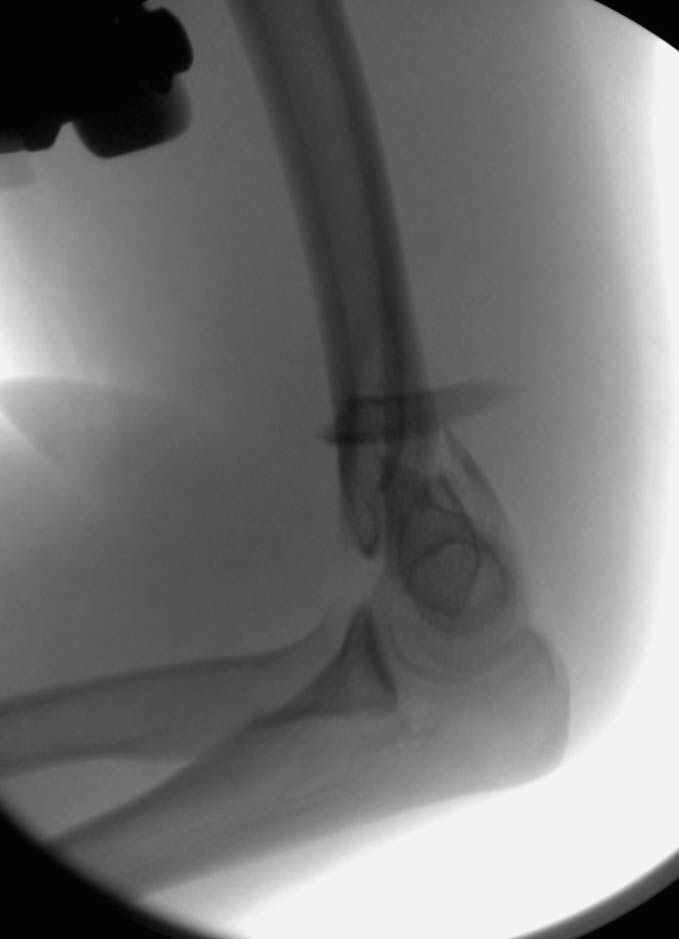

Женщина 42 лет, операция через неделю после перелома.

Д-з - открытый перелом мыщелков со смещзением и локтевой кости

Остеосинтез закрытый (если так можно выразиться), т.е. без

разрезов. Длительность операции - около 1,5 часа со студентом.

6 щелчков ЭОПом.

И как часто вам удается получить такую симпатичную рентгенологическую картинку при Т-образных переломах, особенно с импрессией суставной поверхности? А без ЭОПа? Какого обьема движений достигаете в итоге?